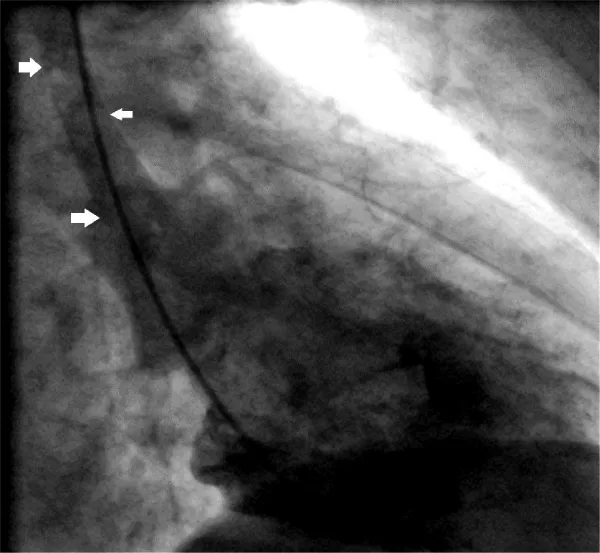

Figure 4: The left coronary artery shows an occlusion of the left anterior descending coronary artery (*) (left anterior oblique projection, RCX: ramus circumflexus).

Download Image

Figure 5: This figure shows left ventriculography and the patient`s aortic dissection (Stanford type A) with the intimal flap (arrows) (right anterior oblique projection).

A 56-year-old obese man with a history of hypertension was admitted at night to the department of cardiology of our hospital because he had developed sudden onset right-sided thoracic pain with radiation into the right shoulder and right arm. He was sweating profusely and had massive nausea. The initially performed 12-lead ECG showed marked inferior ST segment elevations (Figure 1). Beside analgetics and oxygen, he was treated with aspirin, clopidogrel, heparin and the fibrin-specific thrombolytic tenecteplase. His symptoms resolved after 30 minutes. However, half an hour later, he developed left-sided thoracic pain, tachycardia, low blood pressure and the ECG signs of anterior ST-segment elevation myocardial infarction. The performed coronary angiography revealed a normal right coronary artery (Figure 2). The left coronary artery showed a long dissection of a large ramus circumflexus (RCX) (Figures 3,4). Additionally, the left anterior descending coronary artery (LAD) was occluded at about the mid-level (Figure 4, asterisk). Afterwards the left ventriculography revealed a reduced function and a Stanford type A aortic dissection with the intimal flap (Figure 5, arrows). Immediate patient transfer for emergency surgical intervention was arranged. During transport, ventricular fibrillation occurred, and he required endotracheal intubation as well as prolonged cardiopulmonary resuscitation. Unfortunately, he died due to a refractory cardiogenic shock during further transport.